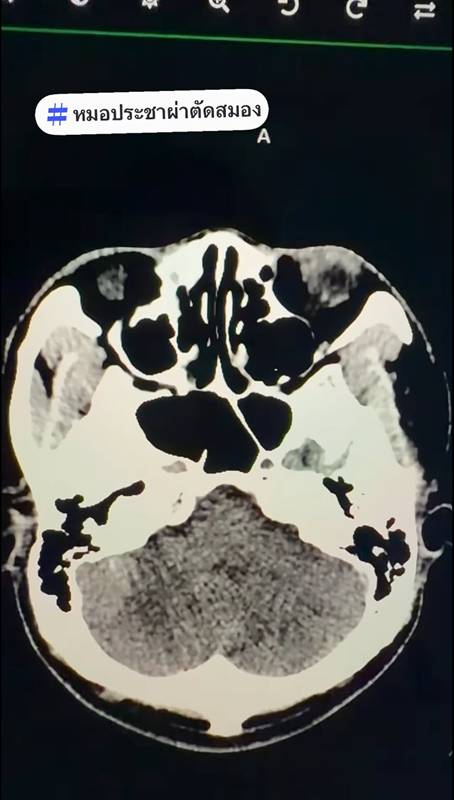

เคสแรก ผู้ป่วยชายอายุ 65 ปี มีแคลเซียมที่เกาะอยู่เต็มลำของหลอดเลือดเลี้ยงก้านสมองและซีรีเบลล่า จึงทำให้เคสนี้มีอาการเวียนหัวไม่หาย 1 สัปดาห์ก่อนมา ภรรยาสังเกตว่าเดินไม่ปกติ ทำ MRI ภรรยาบอกว่าหาสาเหตุไม่เจอ หมอทำการฉีดสีและทำ CTA จะเห็นแคลเซียมเกาะอยู่ที่ Vertebral artery แคลเซียมที่เกาะอยู่ 2 เม็ดนี้เป็นโรคหลอดเลือดสมองMRI ถ้าสมองยังไม่ตาย จะเห็นว่าปกติ ต้องดูหลอดเลือดถึงจะอธิบายอาการได้

แคลเซียมเกาะที่ผนังหลอดเลือด ทำให้รูของ Vertebral artery เล็กลง ขาดเลือด จึงทำให้เวียนศีรษะรุนแรง เดินเซ ทรงตัวไม่ได้ เหตุนี้ต้องทานยาต้านเกล็ดเลือดและยาลดไขมัน เพื่อป้องกันไม่ให้หลอดเลือดสมองตันถาวร เพราะตำแหน่งนี้ถ้าตาย ก็อาจเป็นเจ้าชายนิทราหรือเสียชีวิต

ภาพจาก เฟซบุ๊ก หมอประชาผ่าตัดสมอง